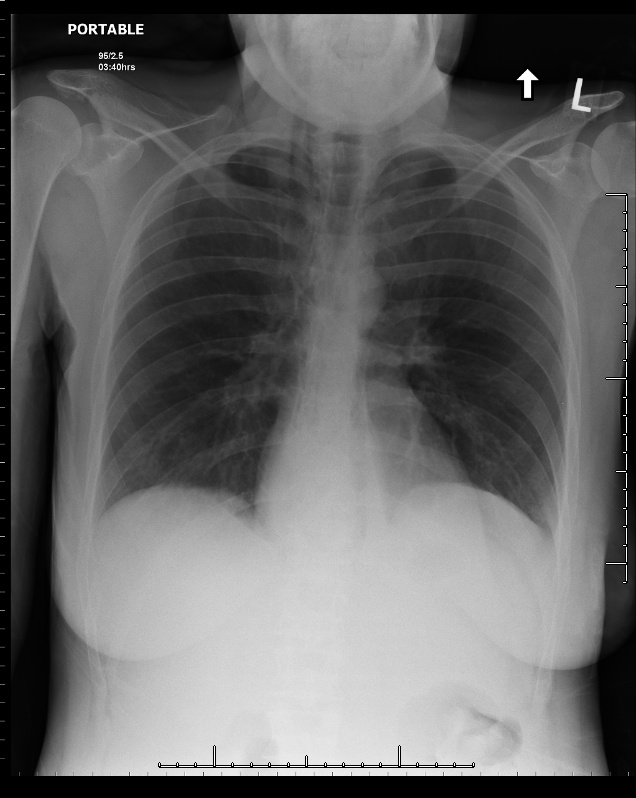

I called the CT technologist in and took a short walk back to the hospital. While the CT was being performed I looked at the patient’s chest x ray. There were subtle linear lucent streaks in the mediastinum …. findings compatible with pneumomediastinum. The ER doc had not noticed them, and looking back as a family physician I likely would not have noted them either.

Figure 2: Chest x ray showing linear lucencies in the mediastinum compatible with pneumomediastinum.

A quick check of the CT pulmonary embolism study revealed no pulmonary embolism, but did confirm the presence of pneumomediastinum, as well as bilateral small pleural effusions and a hiatus hernia.